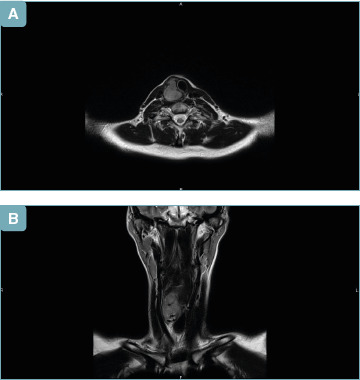

滑膜肉瘤是一种罕见的恶性间质肿瘤,很少发生在头颈部和甲状腺部位。研究人员在文献中只记录了少数病例。我们提出一个病例的年轻女性诊断为滑膜肉瘤起源于甲状腺区域,一年后全甲状腺切除术的原发性乳头状癌和化疗后八年的淋巴瘤。

Synovial sarcoma is a rare malignant mesenchymal neoplasm that rarely arises in the head and neck and thyroid lodge. Researchers have documented only few cases in the literature. We present the case of a young woman diagnosed with synovial sarcoma that originated in the thyroid region one year after a total thyroidectomy for a primary papillary carcinoma and eight years after chemo-radiotherapy for a lymphoma.